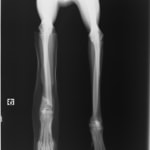

症例3:キルシュナーワイヤーのピンニングによる整復

ペルシャ猫 11ヶ月齢 雄

他院にて左大腿骨遠位の成長板骨折(salter-harrisⅠ型)が認められており、治療相談を目的として来院。当院にて、キルシュナーワイヤーを用いたピンニングにより骨折部位の整復を行いました。術後の経過は良好で、現在も経過観察中です。

術前レントゲン

術後レントゲン